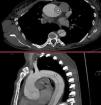

Mujer de 47 años con antecedente de aortopatía bicúspide en abuelo paterno; los padres fallecieron jóvenes en un accidente de tráfico. Por palpitaciones, se solicitó un ecocardiograma ambulatorio, observando un ventrículo dilatado con un diámetro telediastólico del ventrículo izquierdo de 71mm, indexado 3,4mm/m2, fracción de eyección del ventrículo izquierdo del 55-60% además de una válvula aórtica bicúspide con fusión entre los velos coronarianos derecho e izquierdo que condicionaba una insuficiencia aórtica severa (fig. 2) con una raíz aórtica de 40mm. Se solicitó una tomografía computarizada para estudio prequirúrgico (fig. 1) que se realizó tres semanas después, evidenciando una disección aórtica tipoA de Stanford/DeBakeyI con un flap intimal a nivel de la raíz que se extendía longitudinalmente (fig. 3) y de forma espiroidea hasta la arteria ilíaca común izquierda, involucrando el tronco braquiocefálico derecho sin comprometer su flujo. Ante estos hallazgos se trasladó a la unidad de cuidados intensivos cardiológicos para intervención quirúrgica urgente, realizándose cirugía de David con reimplante independiente del tronco braquiocefálico.